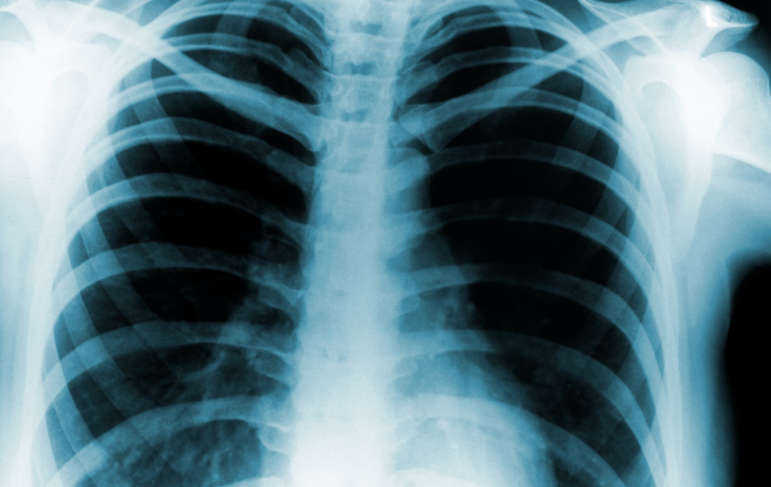

November is Lung Cancer Awareness Month. Lungs are complicated organs that are part of the respiratory system that help people breathe air and bring fresh oxygen into the body. They perform the crucial process of gas exchange where oxygen and carbon dioxide are switched for one another. Lungs are also important because they change air to the proper temperature and humidity level required by the body. The respiratory system also protects the body from harmful substances by coughing and sneezing, filtering incoming air, and swallowing harmful pathogens. The respiratory system also helps people’s sense of smell. Since the lungs are a part of a lot of crucial processes, lung cancer is a devastating diagnosis.